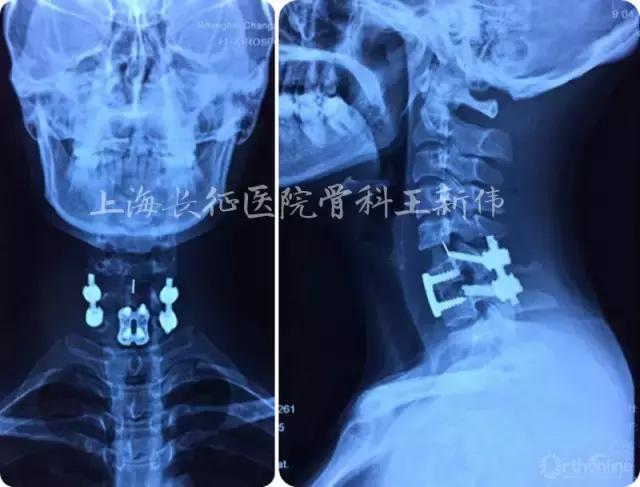

术后颈椎正侧位X线片

术后颈椎MRI平扫,见颈椎曲度及脊髓受压均已恢复

患者术后恢复情况良好,术前颈痛及左上肢麻木无力症状明显改善,双目平视角度改善,术后无特殊不良并发症。术后一周出院,行高压氧康复治疗及四肢肌肉功能康复。